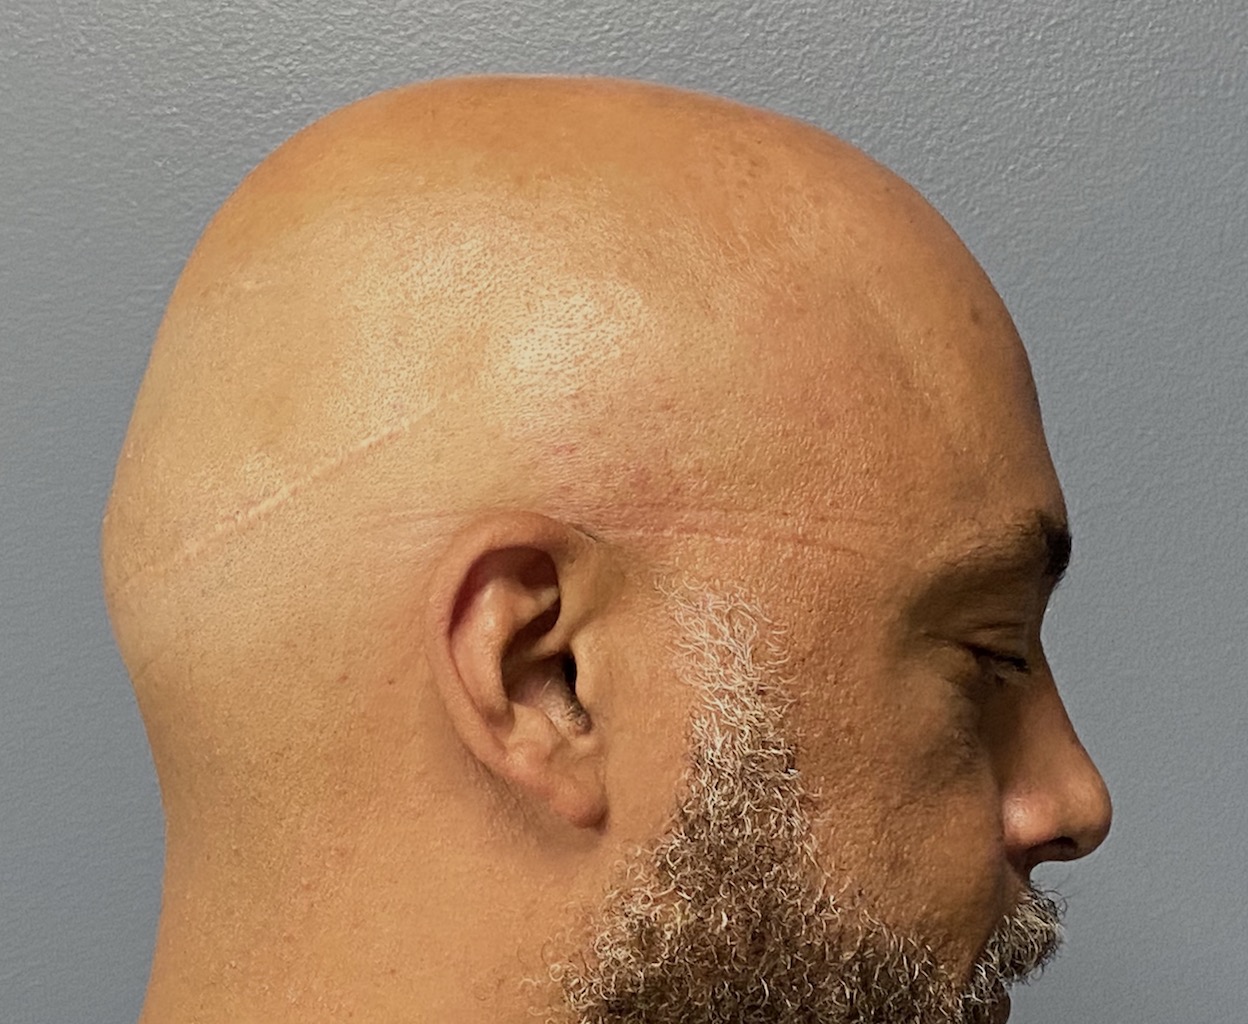

Patient 100

Desire for reshaping of an asymmetric flat back of the head in a shaved head male.

A combined back of the head reshaping procedure was done with a custom skull implant, sagittal ridge reduction and a right temporal muscle reduction.

Desire for reshaping of an asymmetric flat back of the head in a shaved head male.

A combined back of the head reshaping procedure was done with a custom skull implant, sagittal ridge reduction and a right temporal muscle reduction.